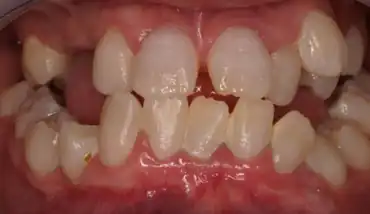

Type I: Radicular type

Type I has been known as radicular dentine dysplasia because the teeth have undeveloped root(s) with abnormal pulp tissue. Morphology and colour of the crown mostly appear normal, but occasionally teeth appear slightly amber coloured or bluish-brown shine in primary teeth with no or only immature root development. The teeth are mostly maligned and have higher risk of fracture.[12]

Clinically the teeth look normal in colour and morphologic appearance; however, they are commonly very mobile and exfoliated prematurely.[3]

Both primary and permanent dentitions can be affected by either type I or type II dentin dysplasia. However, deciduous teeth affected by type II dentin dysplasia have a characteristic blue-amber discolouration, whilst the other dentition appears normal.[3]